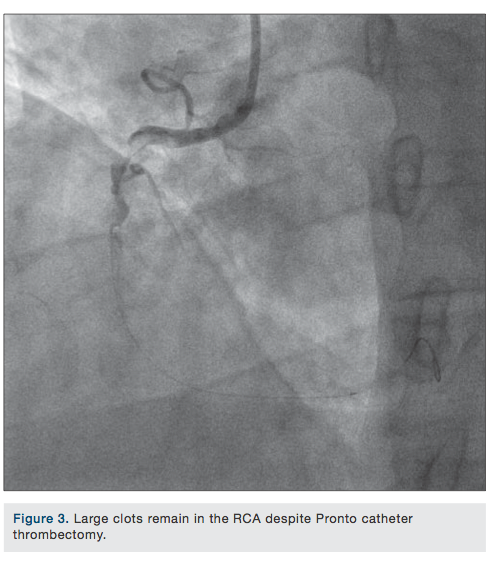

Coronary angiography revealed evidence of severe disease involving the left anterior descending coronary artery (LAD) and the circumflex artery. Right coronary angiography showed a totally occluded right coronary artery filled with a large thrombus (Figure 1). The right coronary artery was successfully cannulated with 0.14 Balance Middleweight (BMW) universal wire (Abbott Vascular) (Figure 2). An unsuccessful attempt was made to perform thrombectomy in the right coronary artery using a Pronto V3 extraction catheter (Vascular Solutions) (Figure 3). At this point, an AngioJet (Medrad/Bayer HealthCare) was inserted and